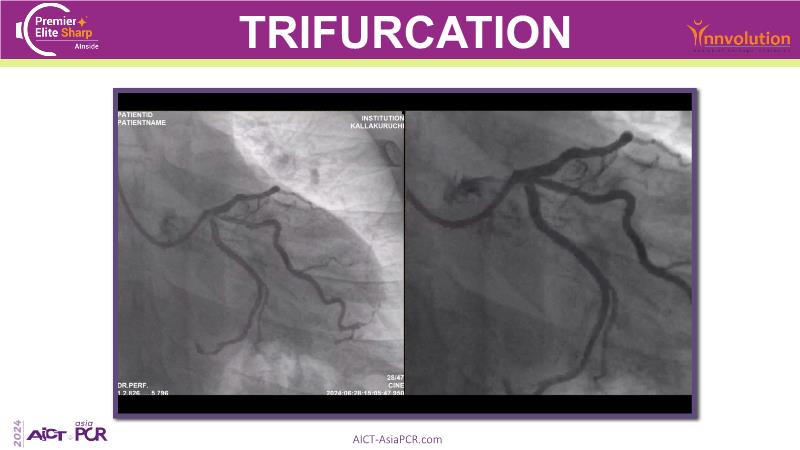

Image-guided PCI of distal left main disease

Exploring a recorded case of image-guided PCI of distal left main disease, as well as a new paradigm in AI-driven imaging, and learn how coronary imaging aids in decision-making, optimises final outcomes, and enhances stent clarity to guide results in complex PCI procedures. Watch now to deepen your knowledge of advanced imaging techniques for better procedural success.